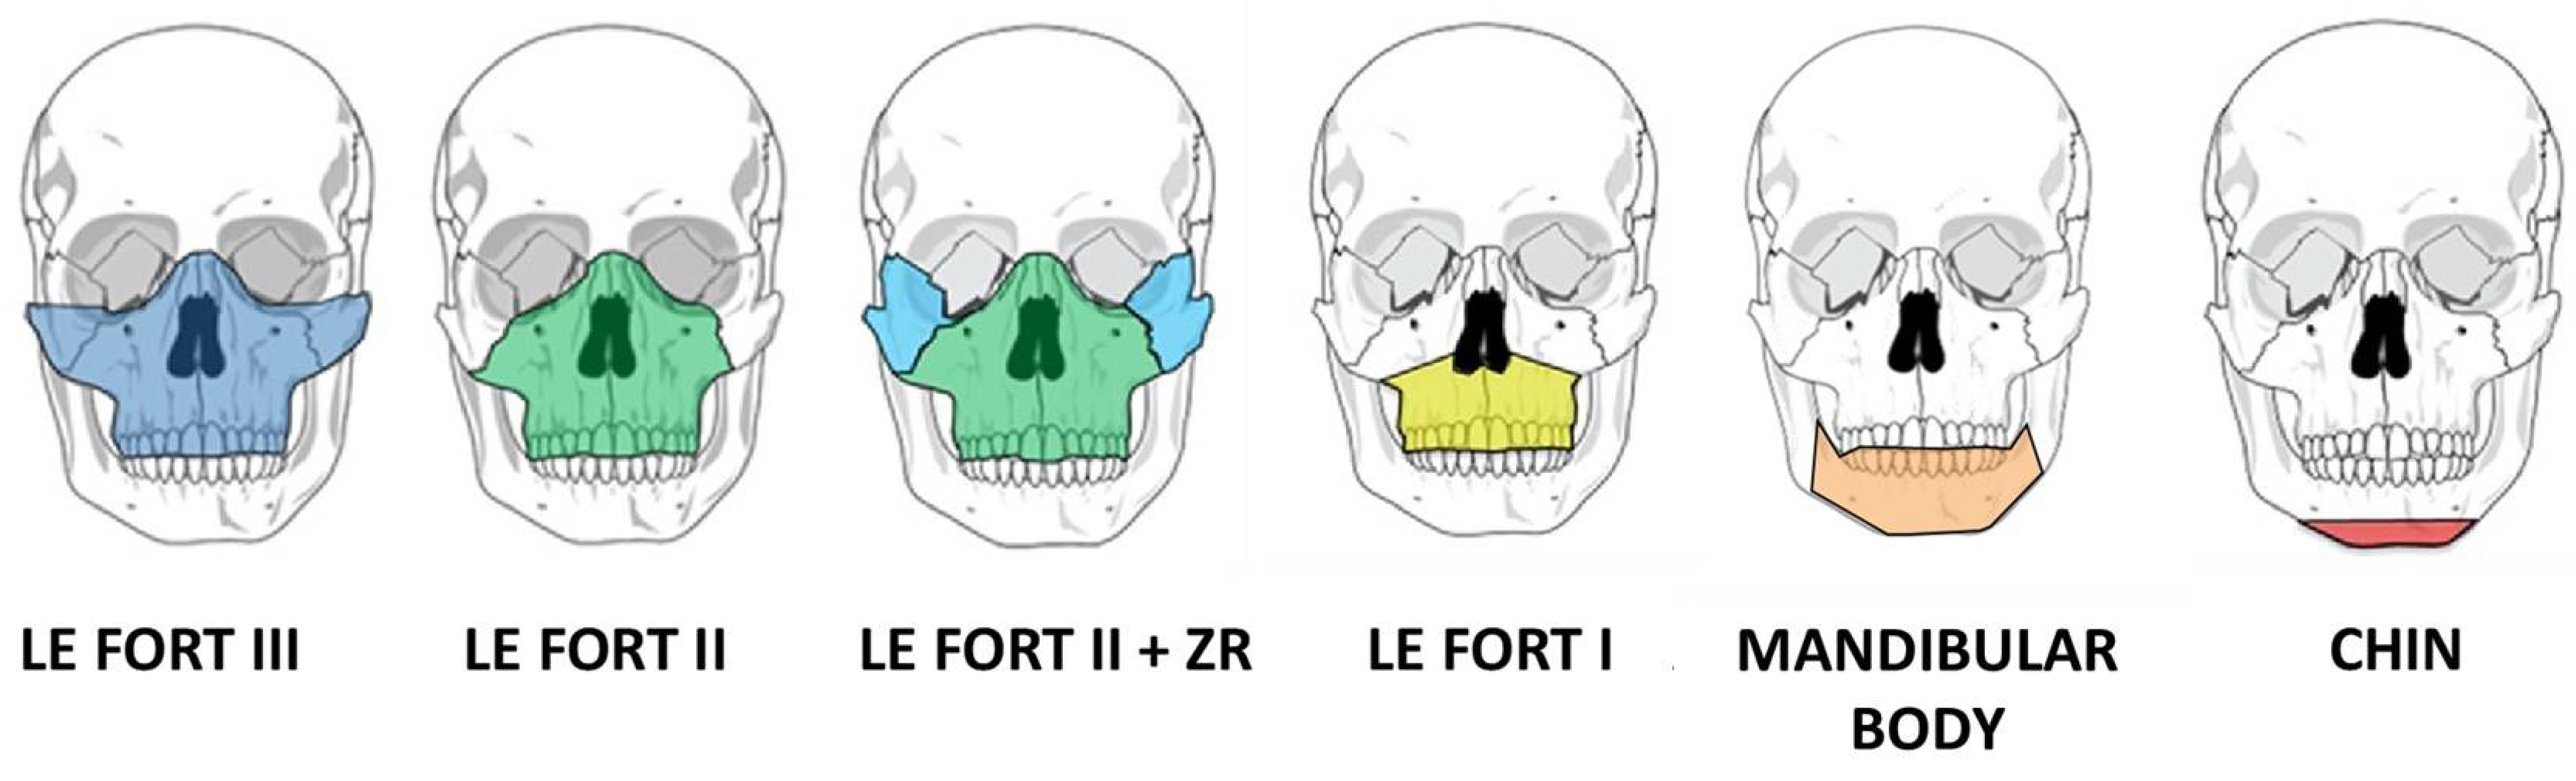

2. Advances in Surgical Planning

5. In-House Computer-Assisted Surgical Planning